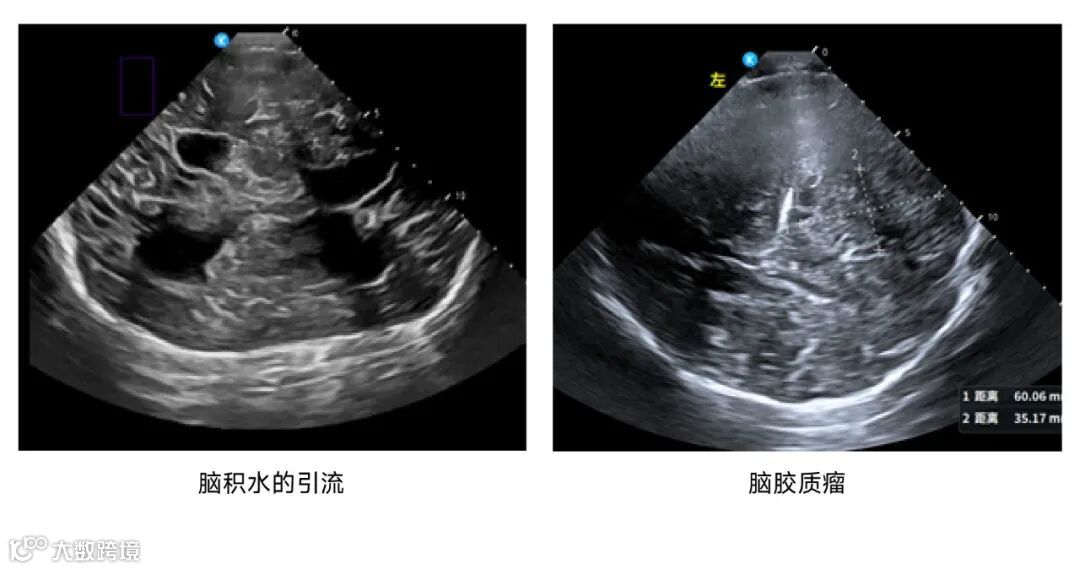

鲲为科技基于kOS带来的超分辨成像技术和超穿探头,

进一步拓展了颅脑超声的应用场景,

在神经内科、神经外科、神经重症监护监测、急诊重症监护、儿科及神经调控等领域带来革命性的创新诊断方案。